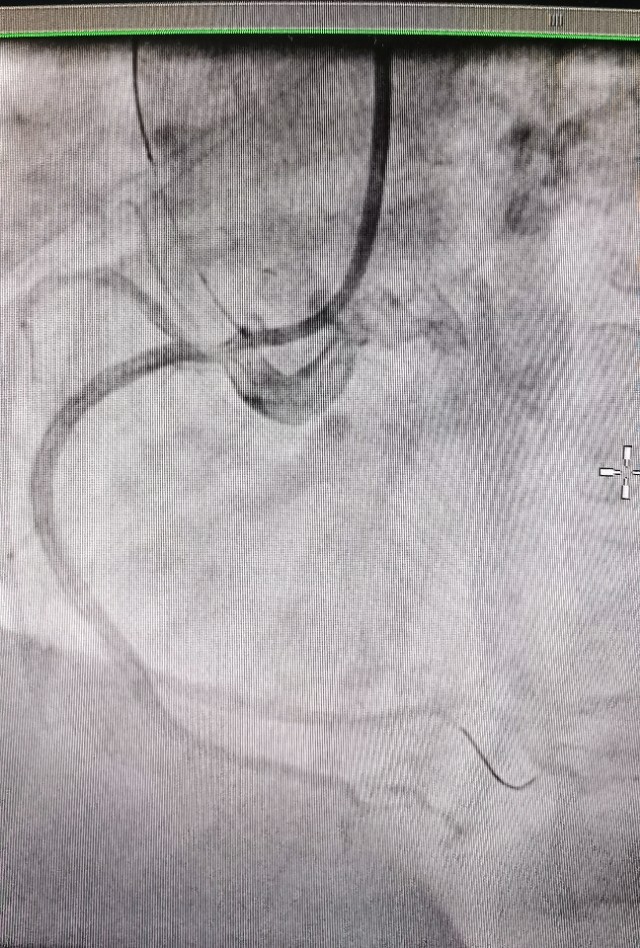

病例2 及时发现ACS斑块,避免心肌梗死发生

中年男性,反复不稳定心绞痛发作,冠脉CTA提示中重度病变,造影发现RCA弥漫病变,OCT发现冠脉内红色,白色血栓形成,随时可能发生心肌梗死!

植入支架后恢复良好,患者胸痛症状消失!